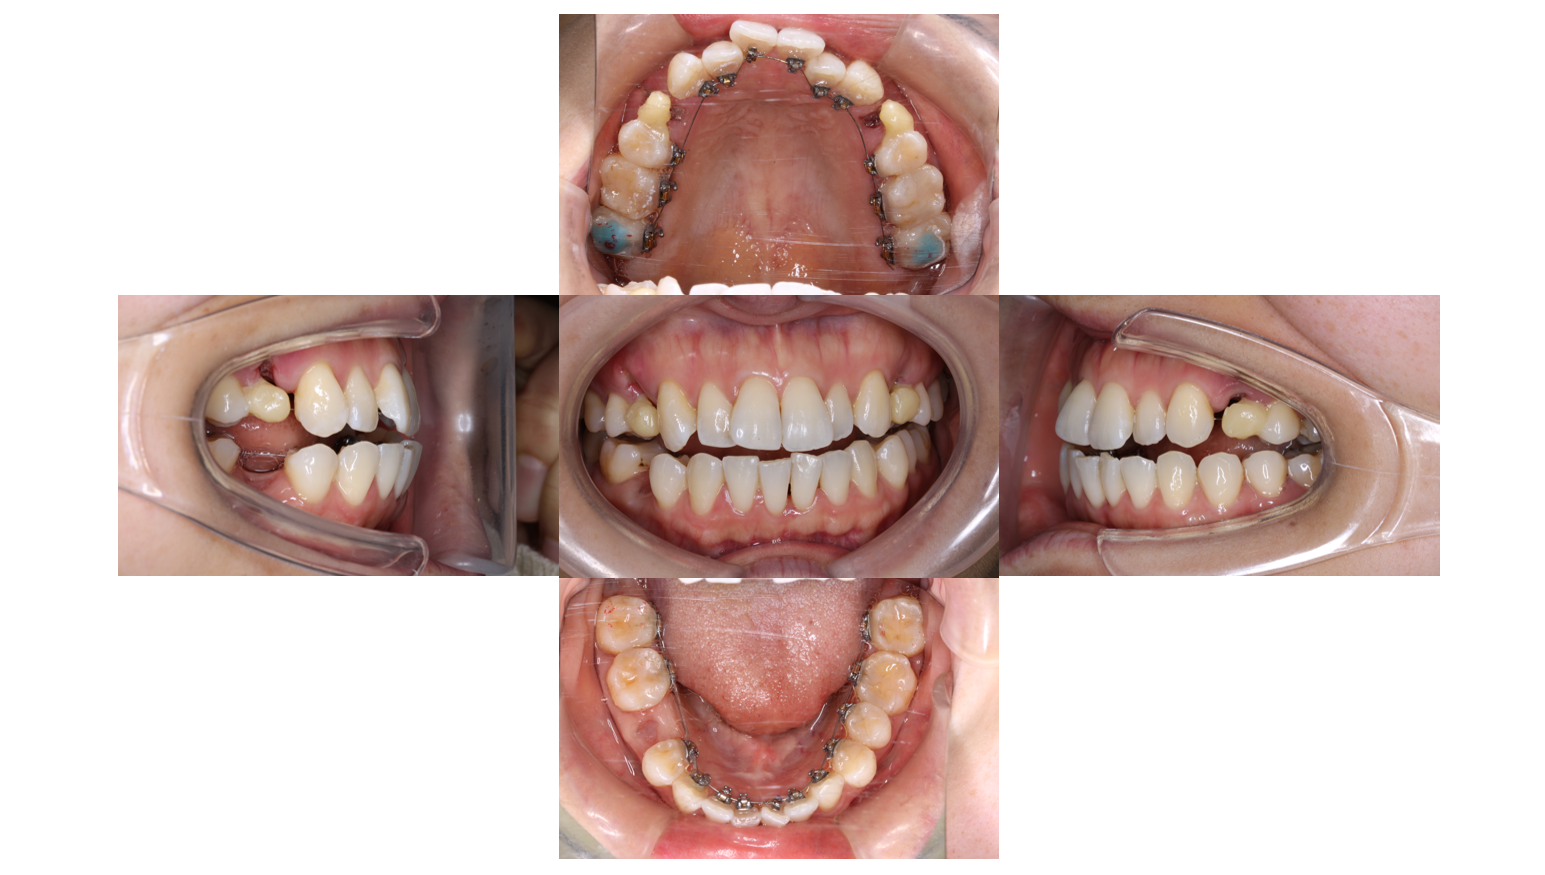

装置装着後

上下裏側に装置がつきました

下の歯と装置が当たらないように青い材料を盛っています